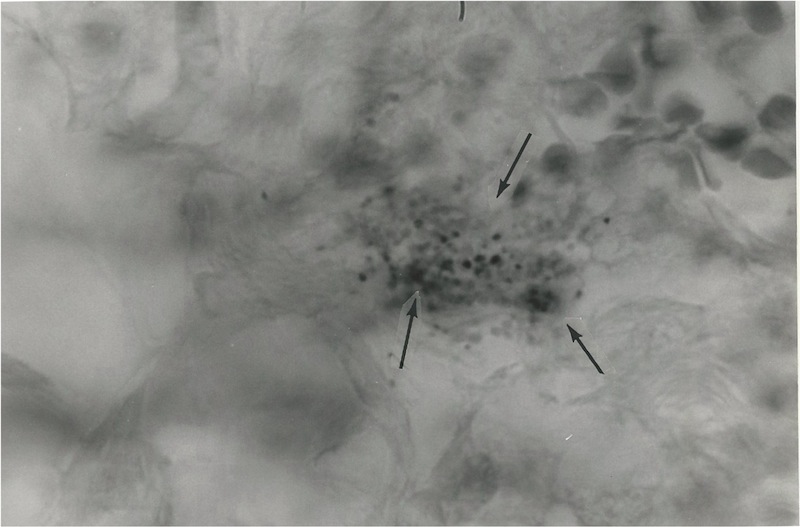

The following

5 photos show the appearance of these coccoid forms in a case of intraductal

breast cancer previously reported in 1981 [8].

Figure

1. Tissue section of breast cancer showing tumor cells and a nest of

extracellular coccoid forms and still smaller “granular” forms, some

of which are barely visible. Intensified Kinyoun (acid-fast) stain,

magnification x 1000, in oil.